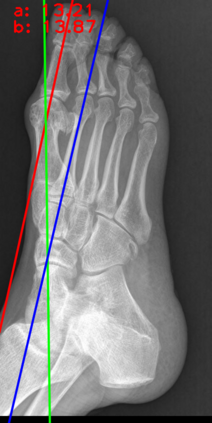

Angular measurements is essential to make a resonable treatment for Hallux valgus (HV), a common forefoot deformity. However, it still depends on manual labeling and measurement, which is time-consuming and sometimes unreliable. Automating this process is a thing of concern. However, it lack of dataset and the keypoints based method which made a great success in pose estimation is not suitable for this field.To solve the problems, we made a dataset and developed an algorithm based on deep learning and linear regression. It shows great fitting ability to the ground truth.